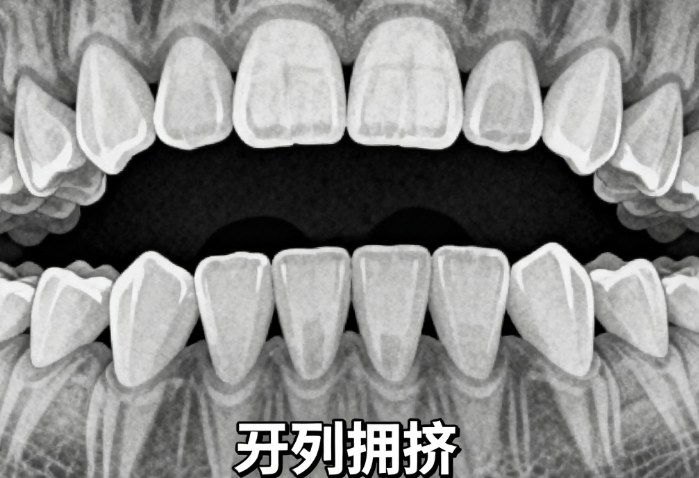

一位18岁患者因牙齿拥挤和龅牙接受隐适美矫正12个月后,牙齿排列整齐,侧貌明显改善,自信心显著提升。